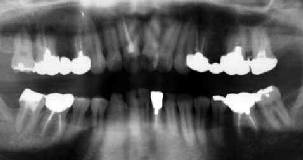

初診時 パノラマ 9年後 パノラマ

中程度以上の歯槽骨吸収を認める

47歳 女性

更に進行したとはいえ、何で抜いた?

初診時口腔内およびX線所見:

カリエスが少なく歯の保存状態は良好ではあったが、清掃状態はやや不良で全体に中程度の 歯槽骨吸収が認められ、歯周疾患傾向が強そうな状態であった。 「4に上行性歯髄炎と思われる骨吸収像が、辺縁部と根尖部に認められた。

処置および経過:

「34根管治療の上、「345 Fop+HAP 施行。「34を連結固定後メインテナンスに移行したが、 そのまま来院が途絶えて9年を経過した。

4|が自然脱落した」と訴えて来院された患者さんのレントゲン写真をみて、愕然とした 怒りにも近い気持ちが交錯した。歯槽骨の吸収が全体に進行して、動揺が認められるように なったのは当時の進行傾向から当然のことである。歯周疾患の進行により抜歯された右下 の大臼歯もさることながら、九死に一生を得た「4を尻目に、比較的健全と思われた「57の 喪失には言葉もない。

「他の歯医者に抜かれてしまいました。何とかして下さい。」と今更いわれても…。 幸いにも、8|が比較的健全な状態であったので、「6部に自家移植をして 「BC5E Bridge装着にて一件落着。